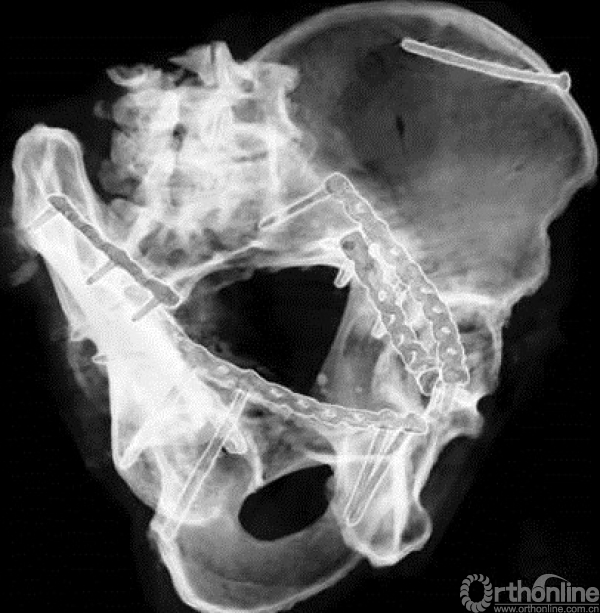

该入路可置放三块钢板

一块为骨盆缘的上侧钢板,一块为骨盆缘的内侧钢板。

一块为方形区(髂坐钢板)

四个重要螺钉

1.骶髂关节前处的螺钉;

2.后柱的螺钉;

3.髋臼柱螺钉;

4.耻骨支螺钉。